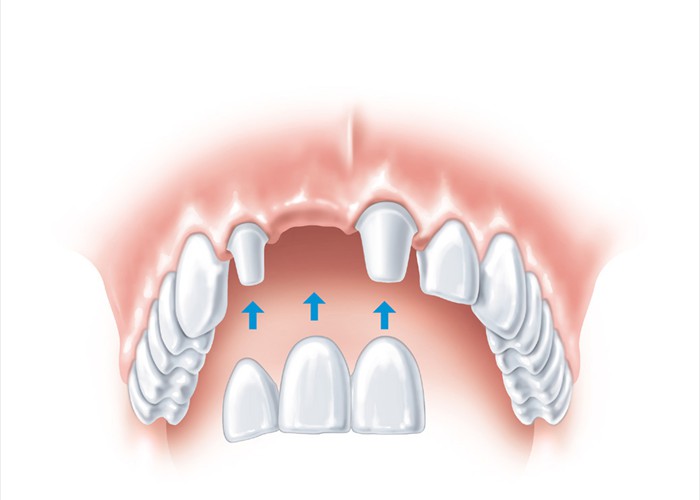

Für die klassische Versorgung mit einer Brücke müssen die Nachbarzähne beschliffen werden. Bei gesunden Nachbarzähnen sollte man dies unbedingt vermeiden.

Für die klassische Versorgung mit einer Brücke müssen die Nachbarzähne beschliffen werden. Bei gesunden Nachbarzähnen sollte man dies unbedingt vermeiden.

Weniger invasiv wäre eine Klebebrücke (Maryland Brücke)

Weniger invasiv wäre eine Klebebrücke (Maryland Brücke)